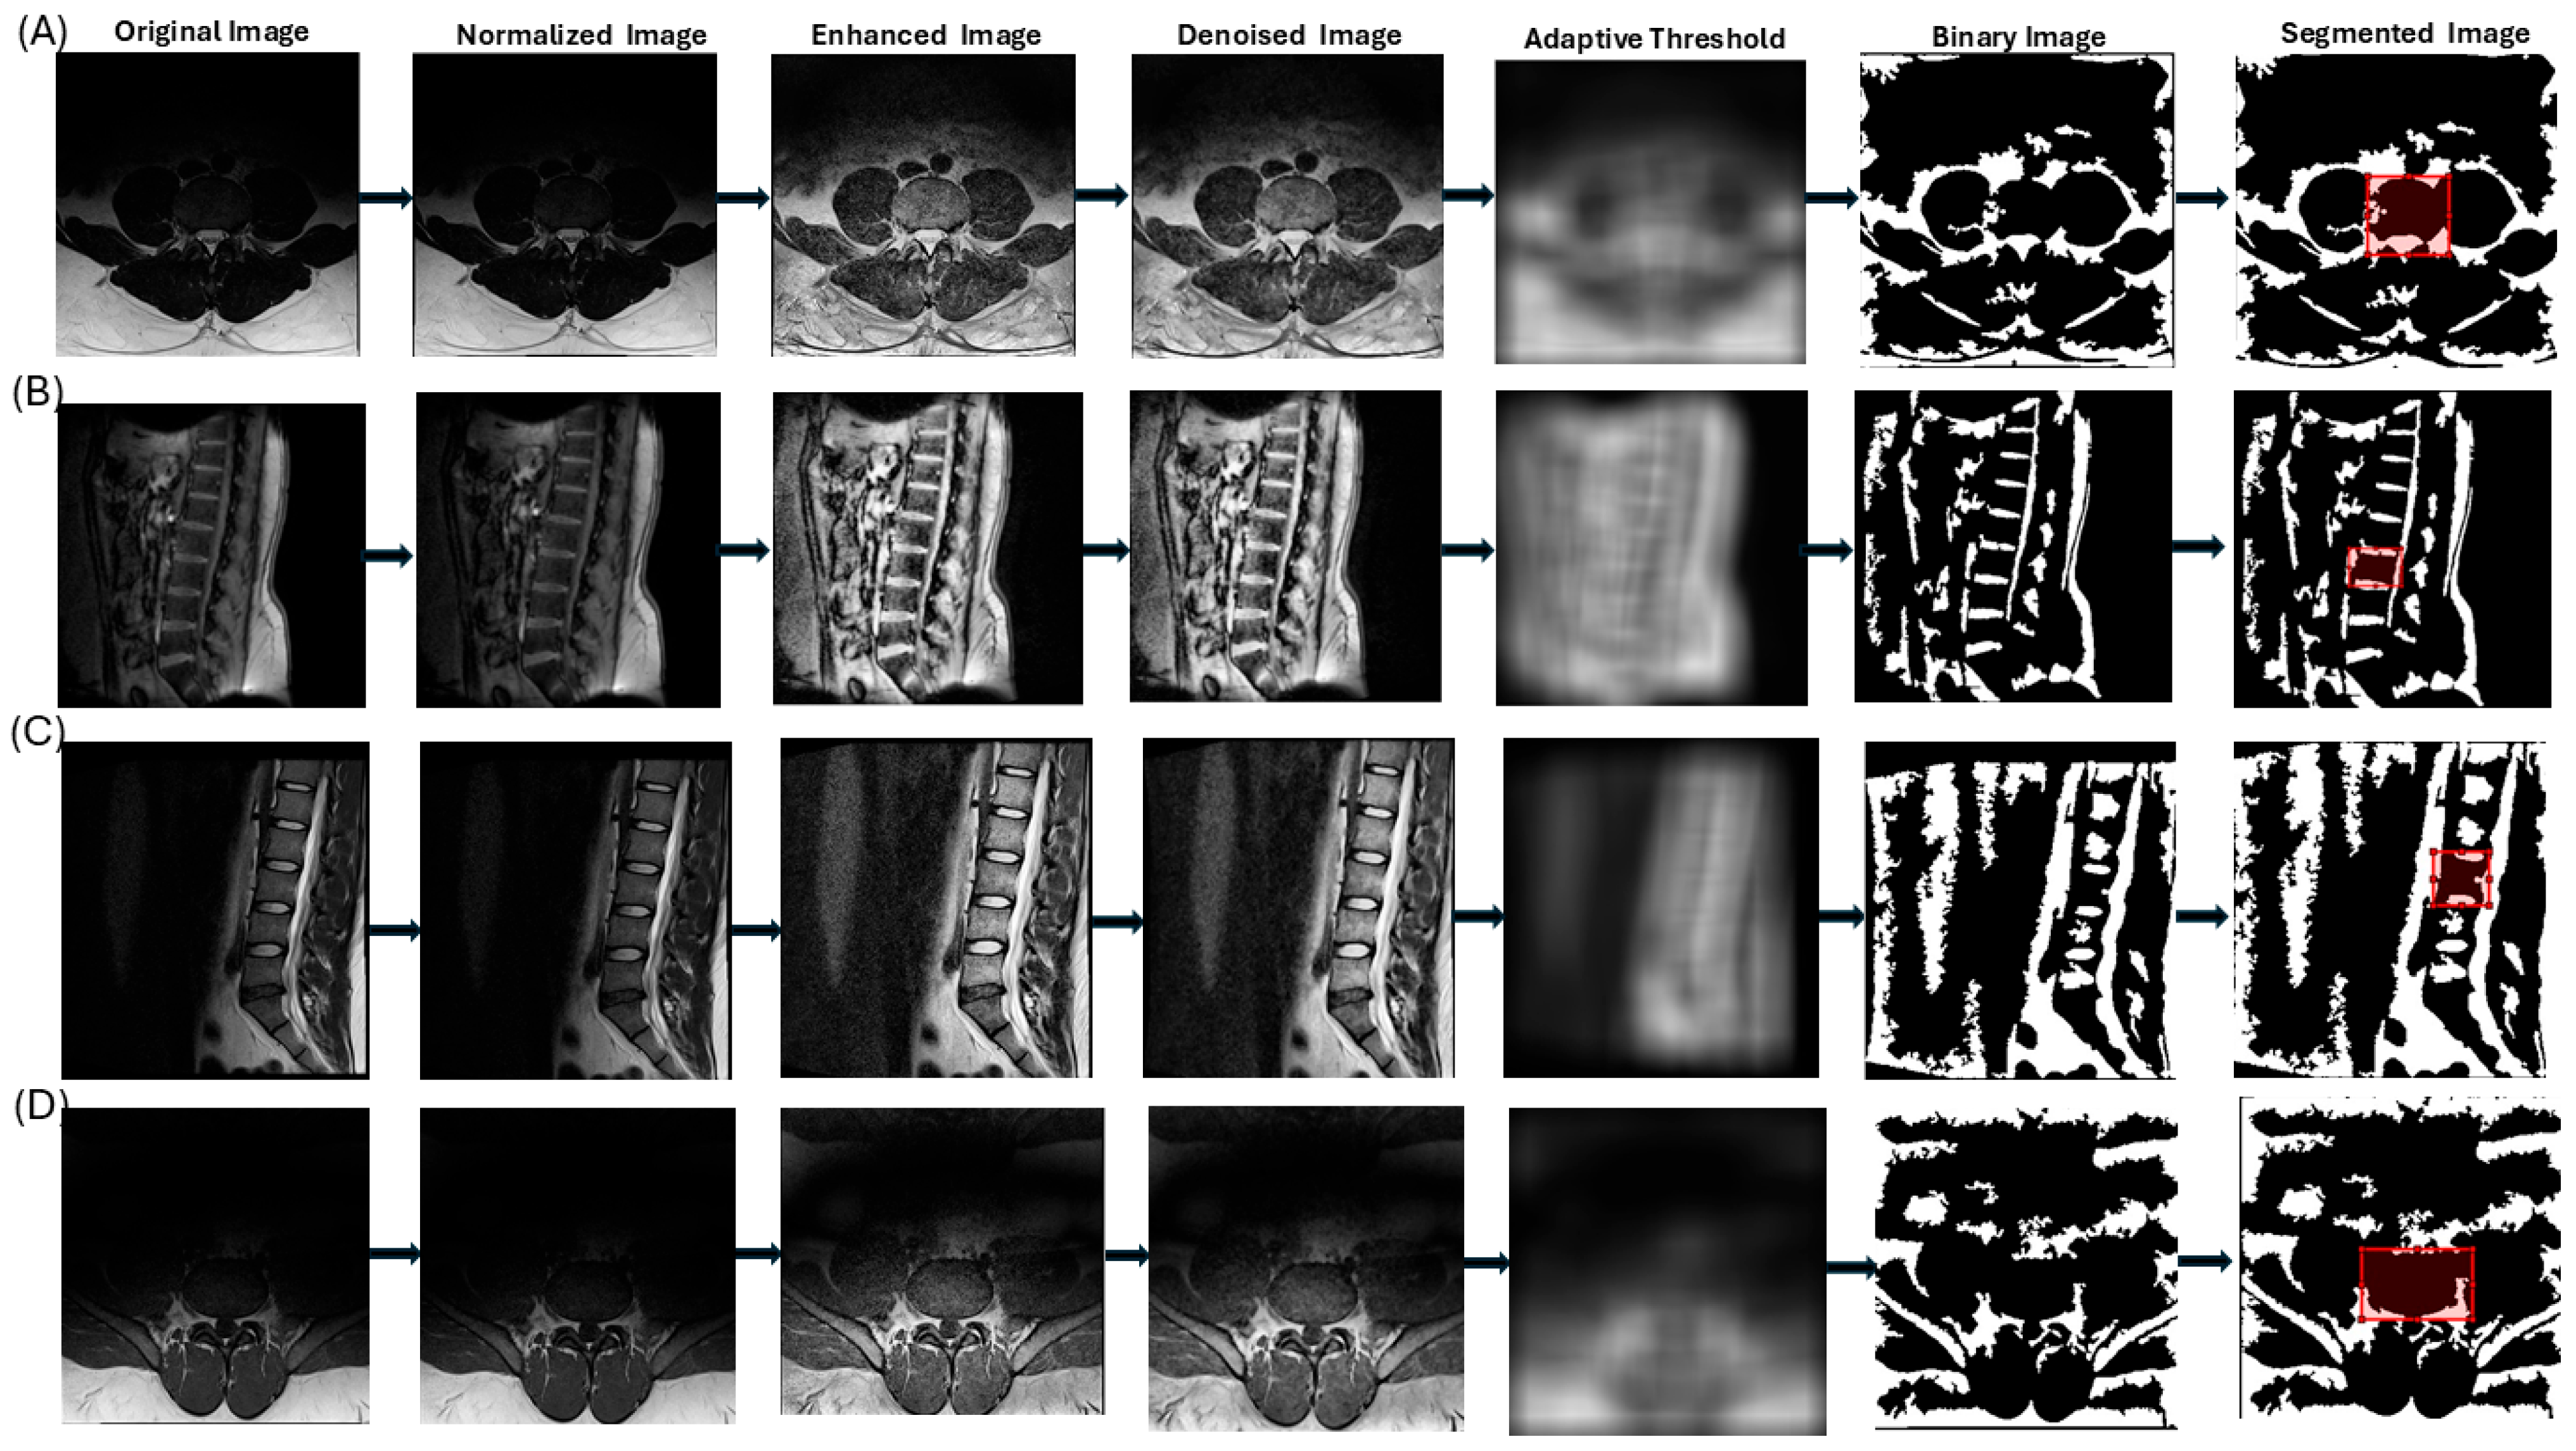

| Step | Description | Purpose | MATLAB Command |

|---|---|---|---|

| 1 | Convert IMA file to DICOM format | Standardize data and extract metadata (e.g., pixel spacing, slice thickness) | dicomread, dicominfo, dicomwrite |

| 2 | Convert image to grayscale | Focus on intensity variations, eliminating color channels | rgb2gray |

| 3 | Normalize image intensities to range (0, 1) | Ensure consistency across images for uniform processing | mat2gray |

| 4 | Enhance contrast by locally redistributing intensities in small regions | Improve visibility of vertebral boundaries with adaptive contrast adjustment | adapthisteq |

| 5 | Reduce noise by replacing each pixel with the median of its 3 × 3 neighborhood | Remove small-scale noise while preserving vertebral edges | medfilt2 |

| 6 | Segment image using adaptive thresholding based on local intensity | Create a binary image, assuming vertebral structures are brighter than the background | adaptthresh |

| 7 | Correct polarity if foreground is darker than background | Ensure vertebral structures are correctly identified as foreground | imbinarize |

| 8 | Apply watershed thresholding to refine segmentation | Delineate boundaries between vertebral structures using a topographic flooding approach | bwdist, watershed |

| 9 | Apply morphological operations to refine segmentation | Remove noise, close gaps, eliminate small objects, and fill holes for structural integrity | imopen, imclose, bwareaopen, imfill |

| 10 | Allow user to draw a rectangular ROI on the segmented image | Enable user-guided selection of the vertebral body of interest | drawrectangle |

| 11 | Create a mask from the ROI and combine it with the segmented image | Isolate the vertebral structure within the user-defined ROI | Logical AND operation |